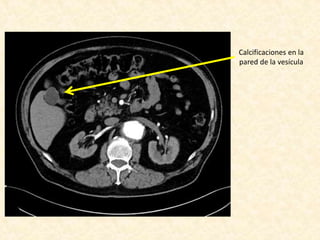

Calcificaciones en la

pared de la vesícula

Informe • Leve dilataciónde arco aórtico • La aorta descendente se presenta elongada, tortuosa y presenta un gran aneurisma que compromete gran parte de su extensión, el cual se inicia aproximadamente 6 cm del origen de la subclavia izquierda, se extiende por aproximadamente 15 cm, y alcanza un diámetro máximo de 10 cm, con trombosis aproximadamente del 60% de la luz. • La aorta abdominal es tortuosa, con ateroma severo de predominio de placas no calcificadas, sin aneurismas. • Estenosis crítica de la arteria renal derecha • Riñones levementes asimétricos por menor tamaño del derecho